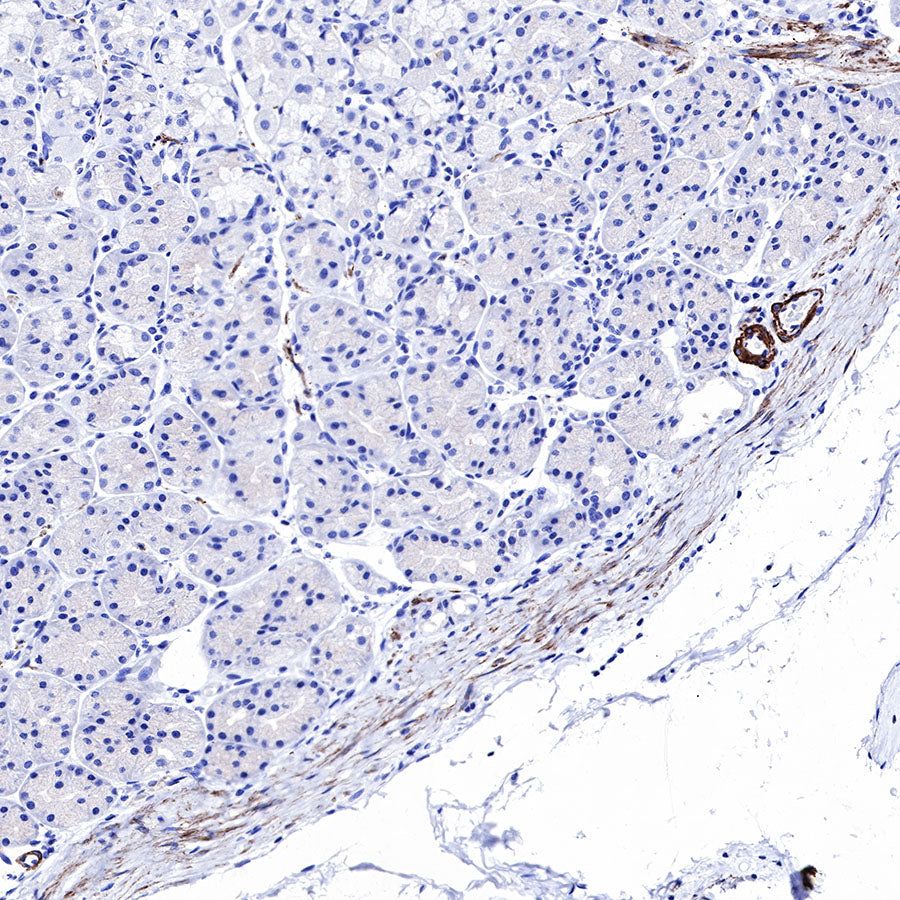

Negative control: IHC shows negative staining in paraffin-embedded human skeletal muscle. Anti-Smooth Muscle Myosin Heavy Chain (SMMHC) antibody was used at 1/1000 dilution, followed by a HRP Polymer for Mouse & Rabbit IgG (ready to use). Counterstained with hematoxylin. Heat mediated antigen retrieval with Tris/EDTA buffer pH9.0 was performed before commencing with IHC staining protocol.